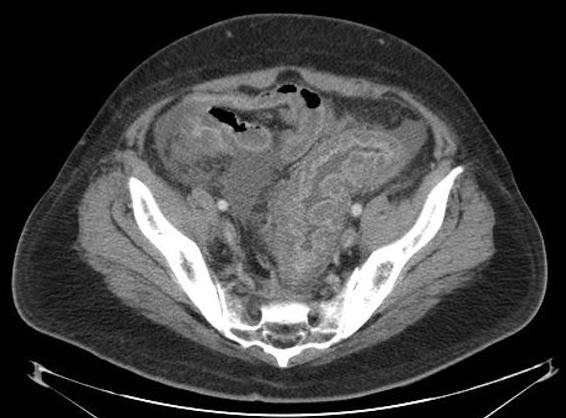

Colite pseudomembraneuse :

Epaisissement de la paroie et des haustrals du colon

ascendant et descendant se forment en aspect

empreinte de pouce au bord du colon . Image

radiologique TDM en coupe coronale |

Epaisissement de la paroi du

colon descendant avec aspect en scie de la muqueuse

du colon . Image radiologique TDM du colon en coupe

coronale . |